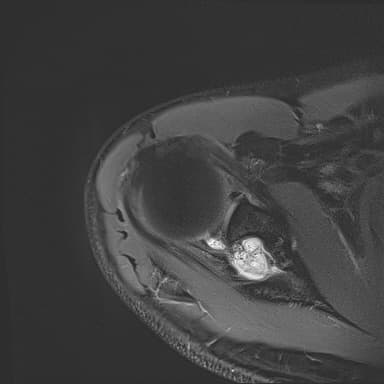

어깨 mri 좀 봐주세요 물혹있다고 하는데 수술해야 하나요?

하도 안 나아서 우측 견관절도 mri 촬영을 했는데 물혹이 있네요

이거 때문에 승모근이 잘 뭉치고 목이 뻣뻣한가요?